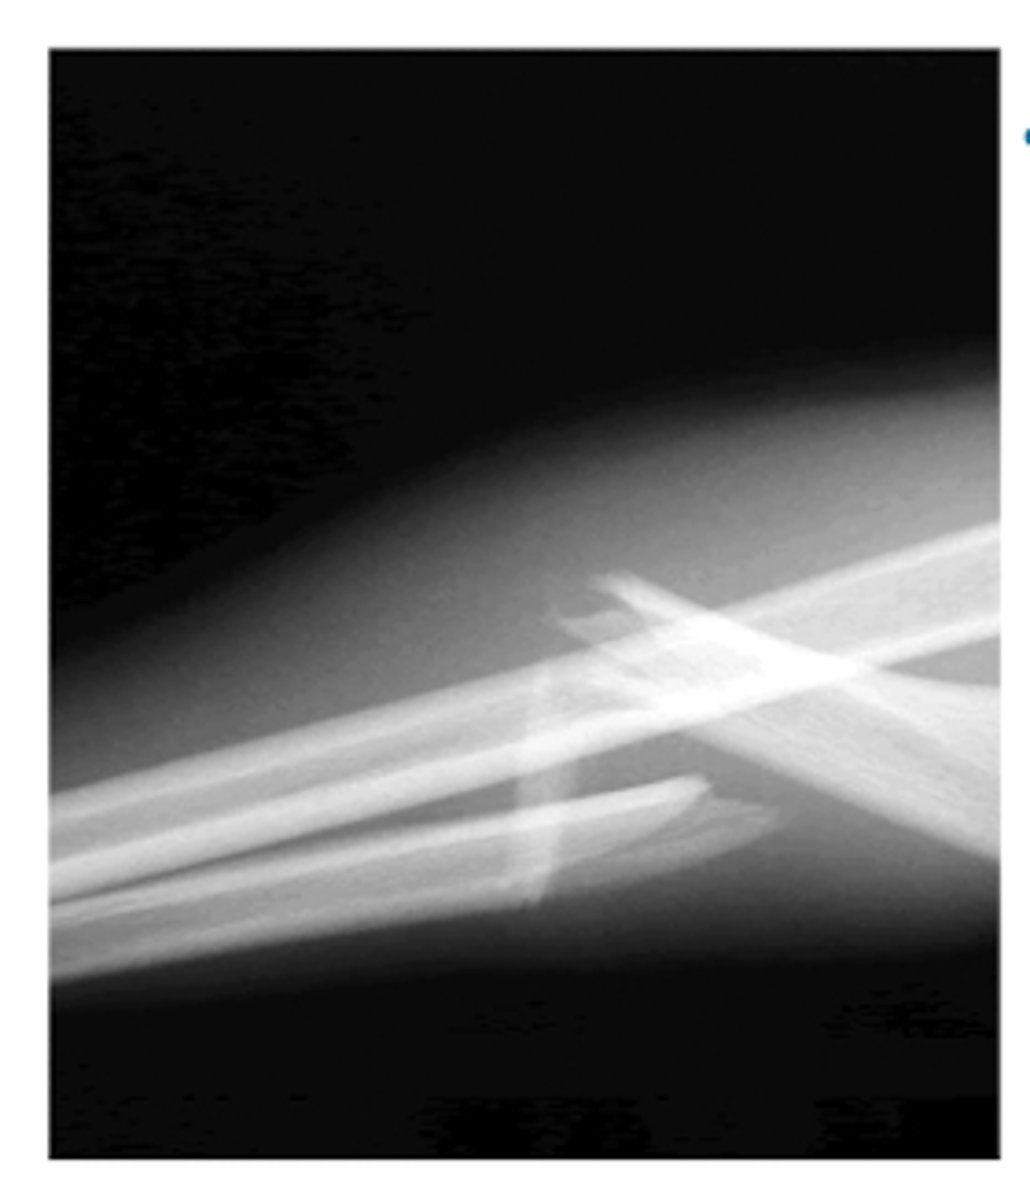

What is a Monteggia fracture?

- dislocation of proximal radioulnar joint

- ulnar fracture

What is the most common type of Monteggia fracture?

Bado Type I

- fracture of the proximal 1/3 ulna

- anterior dislocation of radius

What is a Galeazzi fracture?

fracture of radial shaft

- oblique/transverse Fx

dislocation of the distal radioulnar joint

What is the treatment for Monteggia and Galeazzi fractures in adults vs. children?

Adults → ORIF

- non-surgical Tx has increased risk for displacement

Children → closed reduction and casting